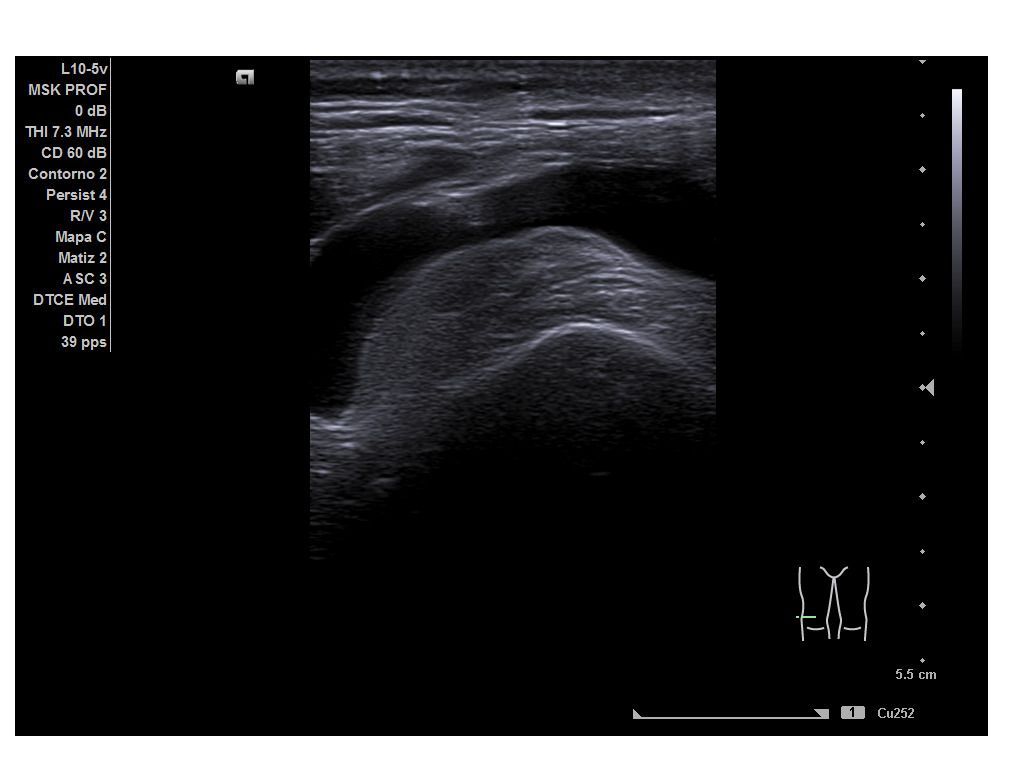

Durante la ecografía se observa una imagen anecoica suprarrotuliana, bajo el tendón del cuádriceps, compatible con una bursitis suprarrotuliana a nivel de la porción medial del cóndilo femoral medial de la rodilla derecha tanto en cortes transversales como longitudinales. Resto de las imágenes obtenidas se encontraban dentro de la normalidad.